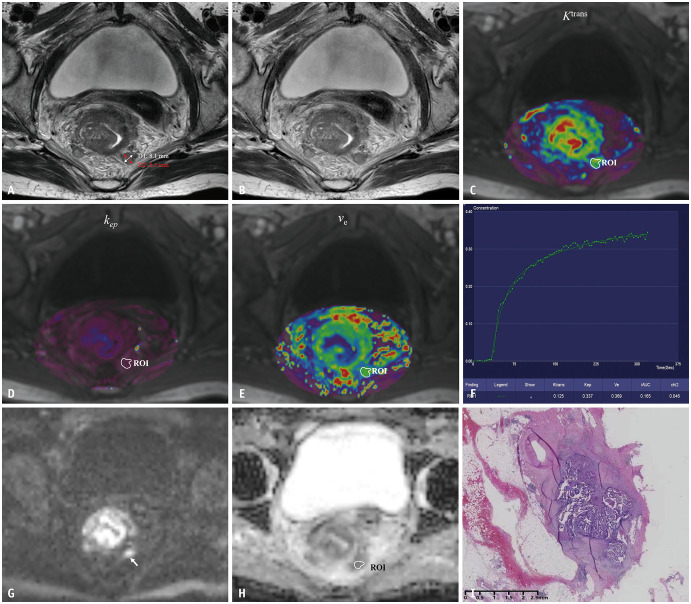

Materials and methods: A retrospective analysis was conducted on 70 patients with rectal cancer, including 168 lesions (70 TDs and 98 MLNs confirmed by histopathology), who underwent pretreatment MRI and subsequent surgery between March 2019 and December 2022. The morphological characteristics of TDs and MLNs, along with quantitative parameters derived from DCE-MRI (Ktrans, kep, and ve) and DWI (ADCmin, ADCmax, and ADCmean), were analyzed and compared between the two groups. Multivariable binary logistic regression and receiver operating characteristic (ROC) curve analyses were performed to assess the diagnostic performance of significant individual quantitative parameters and combined parameters in distinguishing TDs from MLNs.

Results: All morphological features, including size, shape, border, and signal intensity, as well as all DCE-MRI parameters showed significant differences between TDs and MLNs (all P < 0.05). However, ADC values did not demonstrate significant differences (all P > 0.05). Among the single quantitative parameters, ve had the highest diagnostic accuracy, with an area under the ROC curve (AUC) of 0.772 for distinguishing TDs from MLNs. A multivariable logistic regression model incorporating short axis, border, ve, and ADCmean improved diagnostic performance, achieving an AUC of 0.833 (P = 0.027).

Conclusion: The combination of morphological features, DCE-MRI parameters, and ADC values can effectively aid in the preoperative differentiation of TDs from MLNs in rectal cancer.